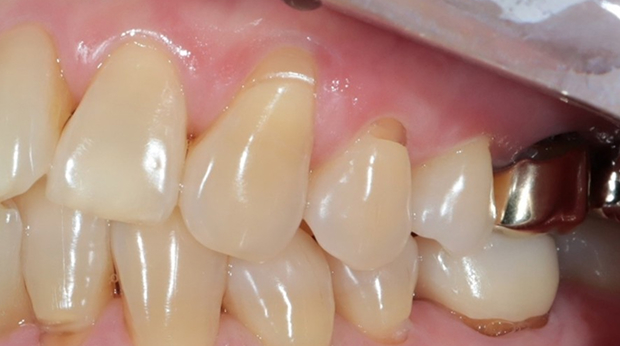

구강외과 진료

라미네이트